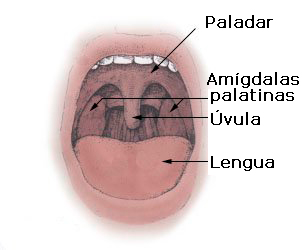

– Glándulas mucosas: aquellas que secretan mucinógenos (sustancia mucosa), que no son más que grandes proteínas glicosiladas que al hidratarse forman una sustancia lubricante y viscosa, de aspecto similar a un gel (la mucina), que es el principal componente del moco. Ejemplo de estas glándulas son las glándulas salivales menores de la lengua y el paladar y las células caliciformes.

Así, estas glándulas participan directamente en el procesamiento de alimentos durante su tránsito por el tracto digestivo, comenzando por la cavidad bucal (con las glándulas salivales) y continuando en el estómago y el intestino delgado (glándulas intestinales y glándulas accesorias del sistema digestivo).

Las glándulas salivales también pueden inflamarse o recrecerse, lo que impide que ejerzan correctamente sus funciones y normalmente lleva al desarrollo de alguna enfermedad. Las paperas son un buen ejemplo de inflamación por infección viral de la glándula parótida en la cavidad bucal.